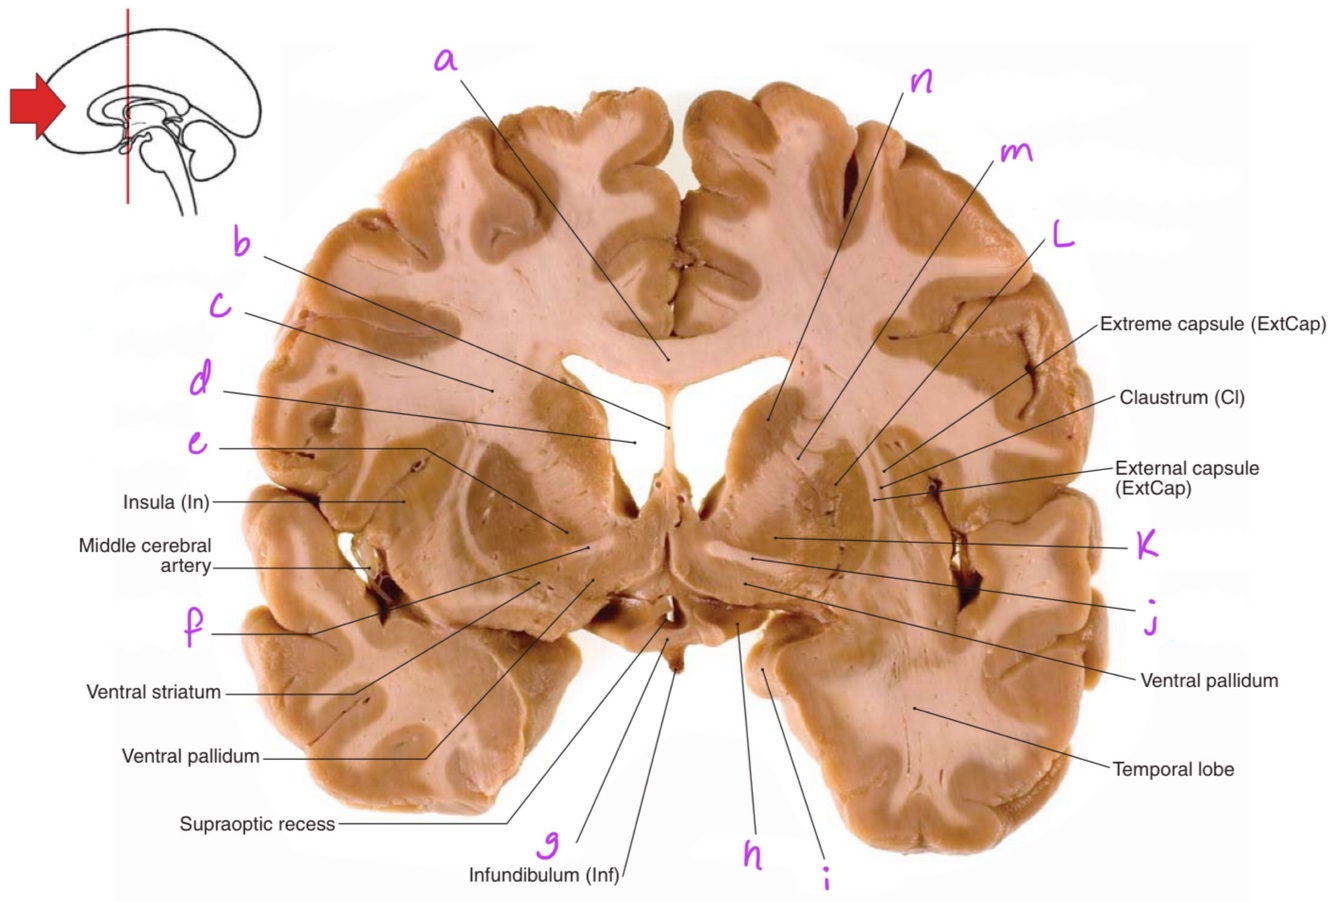

1

a

body of corpus callosum

b

Anterior horn of lateral ventricle

3

c

4

d

5

6

f

7

g

8

h

9

10

septum pellucidum

11

Corona radiata

12

13

e

Globus pallidus

14

Anterior commissure

15

Optic chiasm

16

Optic tract

17

i

Uncus

18

j

19

k

20

L

Putamen

21

m

Anterior limb of internal capsule

22

n

Head of caudate nucleus